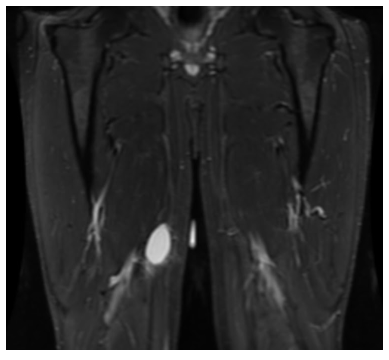

Radiographic imaging is used to help form a diagnosis. These include X-Ray, MRI, CT and Bone Scans

An example of an MRI is shown.